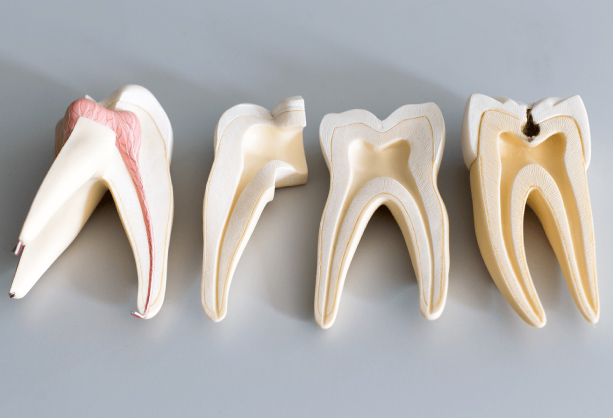

Symptoms indicating the need for a root canal include persistent tooth pain, prolonged sensitivity to heat or cold, gum swelling, and discoloration of the tooth. The procedure helps relieve pain, eliminate infection, and preserve the tooth, preventing the need for extraction.

Warning signs for Root Canal Treatment

Persistent Tooth Pain

Ongoing or severe pain in the

affected tooth.

Tooth Discoloration

Noticeable darkening or

discoloration of the tooth.